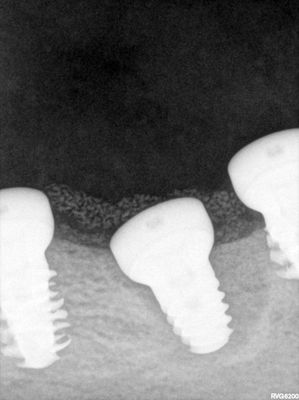

Bone loss noted, bone graft required, upon flapping, decided to place implants. Difficult case due to very strong macroglossic tongue, limited sulcular space. Short and wide implants placed, all socket/defects grafted with sticky bone from cortical allograft. membrane placed interimplant and fibrin membrane also used